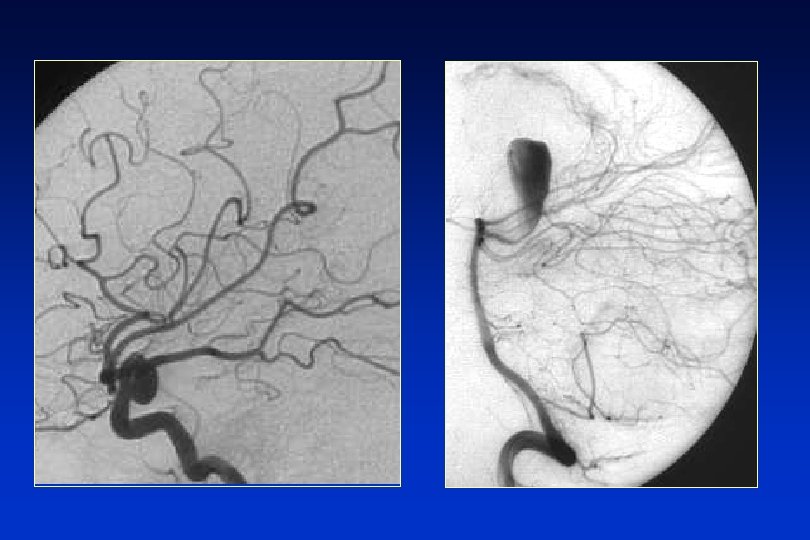

HSA ETIOLOGÍA • Aneurismas arteriales: • Saculares o congénitos. • Fusiformes o arterioscleroso. • Micóticos. • Otras malformaciones vasculares: • HSA no-aneurismáticas: • HSA traumáticas:

ANEURISMAS INTRACRANEALES l Dilataciones localizadas de la pared de las arterias l Suelen situarse en el espacio subaracnoideo de la base del craneo. l 80 -90% de ellos son aneurismas saculares o congénitos. l Su localización más frecuente es la arteria comunicanterior, seguido de la comunicante posterior, cerebral media y tronco basilar; con un claro predominio en la circulación anterior, origen de más del 80%. l En el 20% de los casos los aneurismas son múltiples.

EXPLORACIONES COMPLEMENTARIAS l Tomografía computerizada: La sensibilidad de la TC > 90% primeras 24 horas. l Patrones aneurismáticos. l HSA perimesencefálica. l Sospecha y TC negativa: punción lumbar (PL) l Angiografía: FUNDAMENTAL q Lo más pronto posible. q Terapia endovascular.

HSA TRATAMIENTO: medidas específicas l Prevención del resangrado: l Exclusión del aneurisma mediante cirugía l Exclusión del aneurisma por terapia endovascular l Fármacos antifibrinolíticos